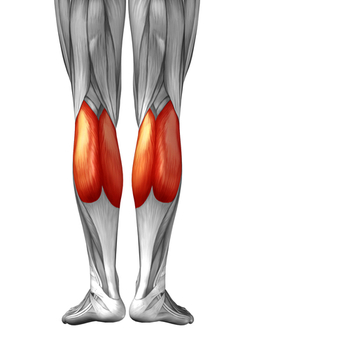

비복근

비복근은 대퇴골의 내외과에서 기시하여 아킬레스건으로 이어집니다. 무리한 산행, 과도한 점프 등과 같이 발목을 강하게 족저굴곡하면 통증이 나타날 수 있습니다.

근복부에 통증으로 나타나기도 하고 아킬레스건, 오금 부위로 통증을 호소하기도 합니다.

치료 포인트는 내외측 비복근을 구분하여 근복부에서 치료를 하거나 골접합부에 통증이 심할 때에는 오금 부위에서 직접 치료하기도 합니다.